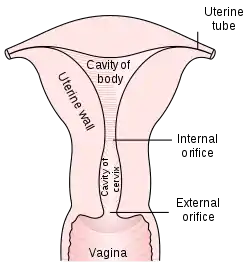

The Papanicolaou test (abbreviated as Pap test, also known as Pap smear (AE),[1] cervical smear (BE), cervical screening (BE),[2] or smear test (BE)) is a method of cervical screening used to detect potentially precancerous and cancerous processes in the cervix (opening of the uterus or womb) or, more rarely, anus (in both men and women)[3]. Abnormal findings are often followed up by more sensitive diagnostic procedures and, if warranted, interventions that aim to prevent progression to cervical cancer. The test was independently invented in the 1920s by the Greek physician Georgios Papanikolaou and named after him. A simplified version of the test was introduced by the Canadian obstetrician Anna Marion Hilliard in 1957.

A Pap smear is performed by opening the vagina with a speculum and collecting cells at the outer opening of the cervix at the transformation zone (where the outer squamous cervical cells meet the inner glandular endocervical cells), using an Ayre spatula or a cytobrush. The collected cells are examined under a microscope to look for abnormalities. The test aims to detect potentially precancerous changes (called cervical intraepithelial neoplasia (CIN) or cervical dysplasia; the squamous intraepithelial lesion system (SIL) is also used to describe abnormalities) caused by human papillomavirus, a sexually transmitted DNA virus. The test remains an effective, widely used method for early detection of precancer and cervical cancer. While the test may also detect infections and abnormalities in the endocervix and endometrium, it is not designed to do so.

The health care worker begins by inserting a speculum into the woman's vagina, which spreads the vagina open and allows access to the cervix. The health care provider then collects a sample of cells from the outer opening or external os of the cervix by scraping it with either a spatula or brush.[54]